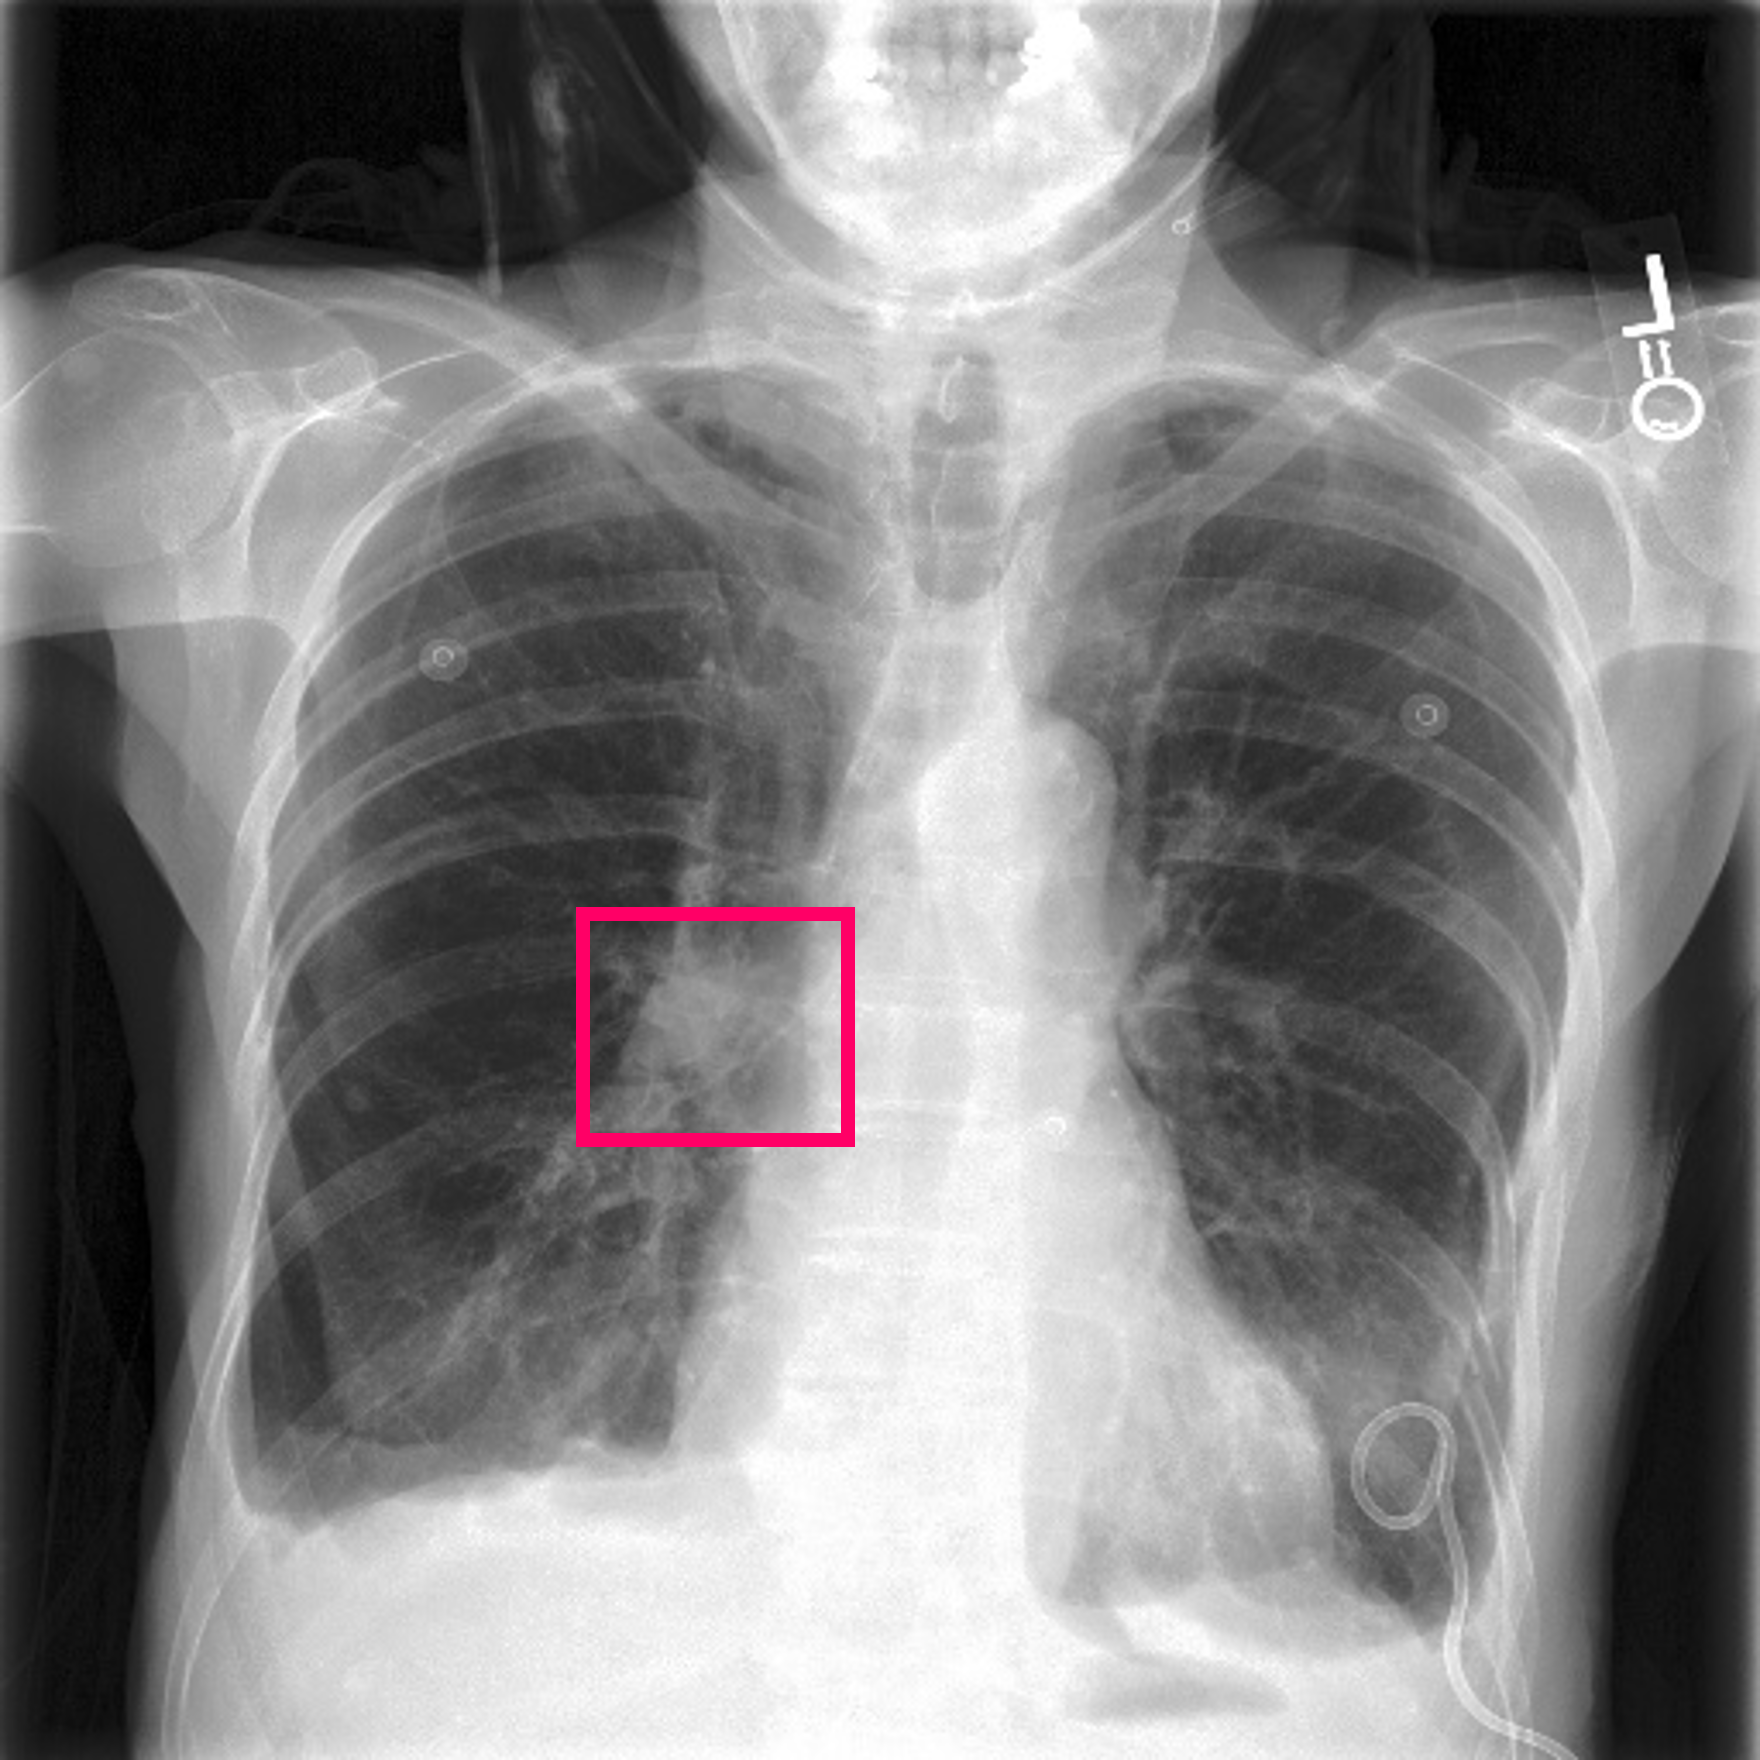

3.3 Interpretability

Post-Hoc Comparisons. We compare our concept-based explanations to post-hoc XAI techniques LIME and SHAP, applied to the baseline InceptionV3 model. The image explanations generated by these techniques disagree with each other and the medical ground truth. We show an example of this observation in Figure 7, where both techniques fail to capture the large mass in the X-ray, and highlight irrelevant regions such as areas outside of the lung as incorrectly important to the classification decision. In contrast, our approach correctly identifies the presence of a mass. More examples are shown in Figure 10.

Refer to caption

(a) Ground Truth

(b) LIME

(c) SHAP

(d) CXR-LLaVA Generated Report

(e) Our Approach

Figure 7: Example of our explanation approach outperforming LIME, SHAP and CXR-LLaVA. Ground truth (a) is a “Large right upper zone mass". LIME (b) and SHAP (c) fail to capture the mass in the X-ray. Most important image regions are bounded by yellow for LIME, and shown in more vibrant green for SHAP. CXR-LLaVA (d) generates a report which wrongly describes the image as non-cancerous. Our approach (e) correctly identifies the presence of a mass.